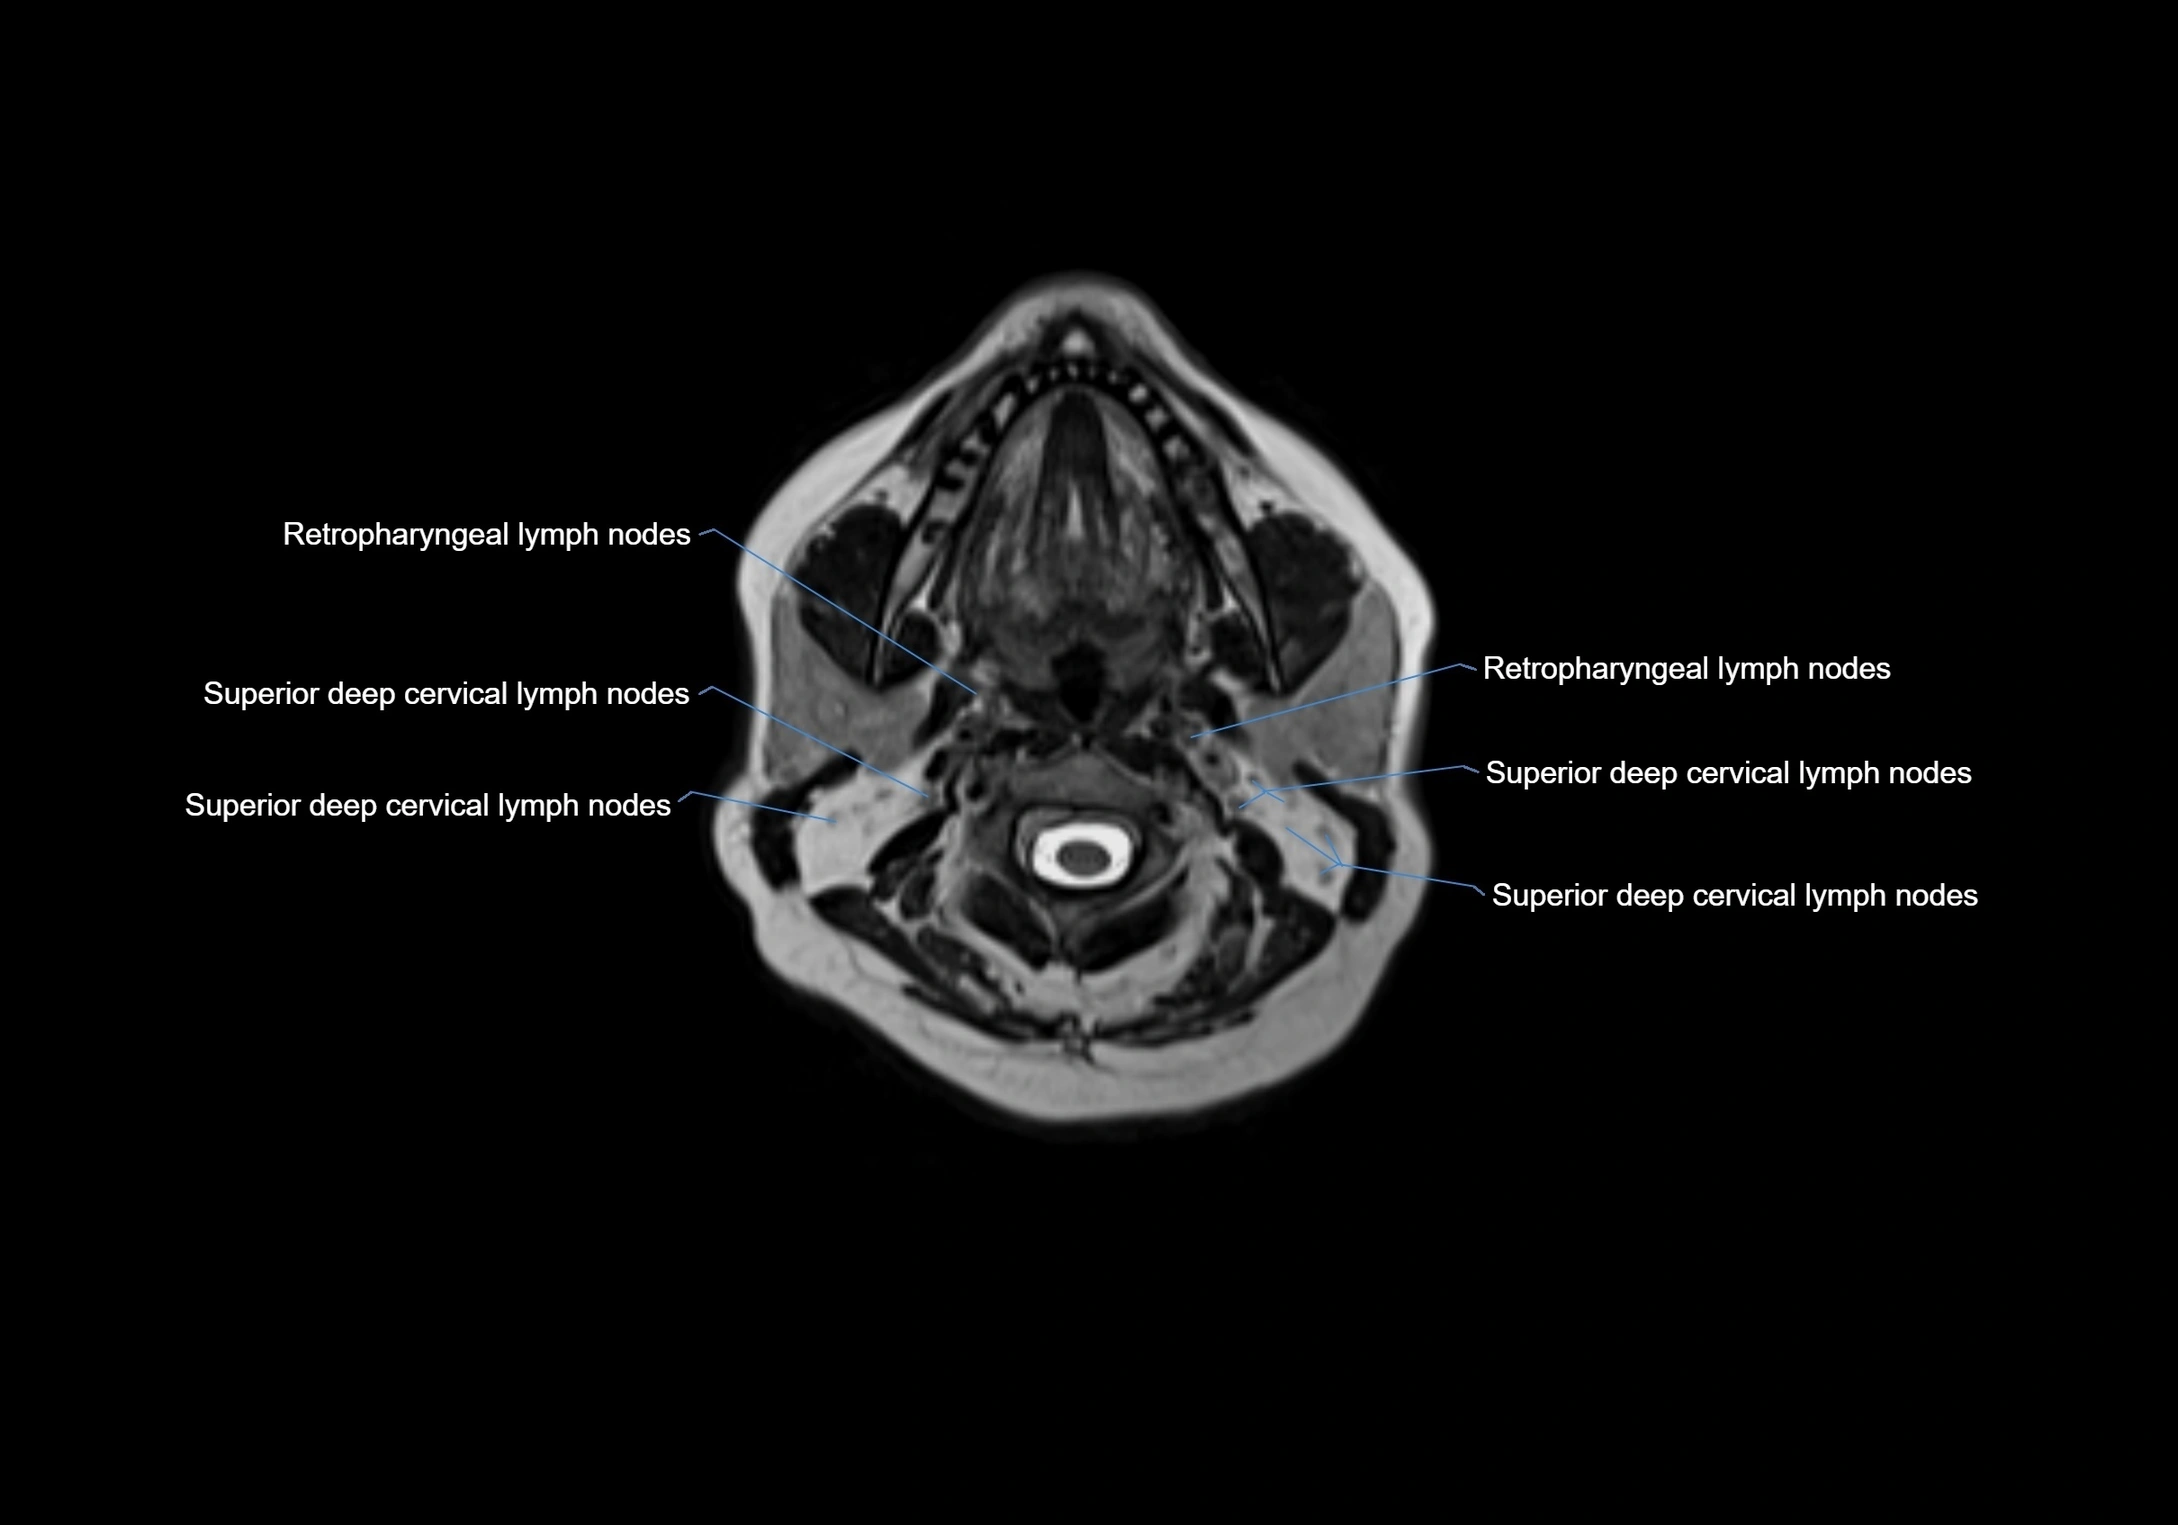

Location

• Found along primary lymph node chains, including preauricular, submandibular, parotid, and occipital regions

• Embedded in subcutaneous fat or superficial fascia, often lateral or posterior to primary nodes

• Variable in number; may occur unilaterally or bilaterally, depending on individual anatomy

MRI images

image